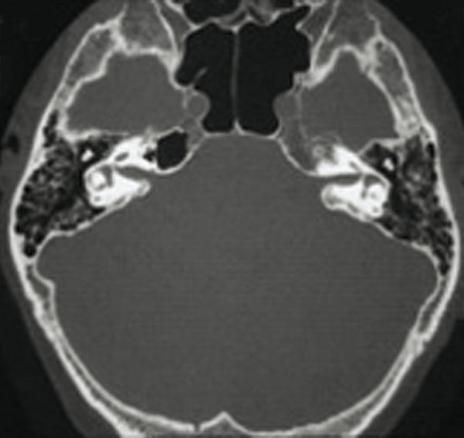

Tomodensitométrie des rochers (coupes axiales)